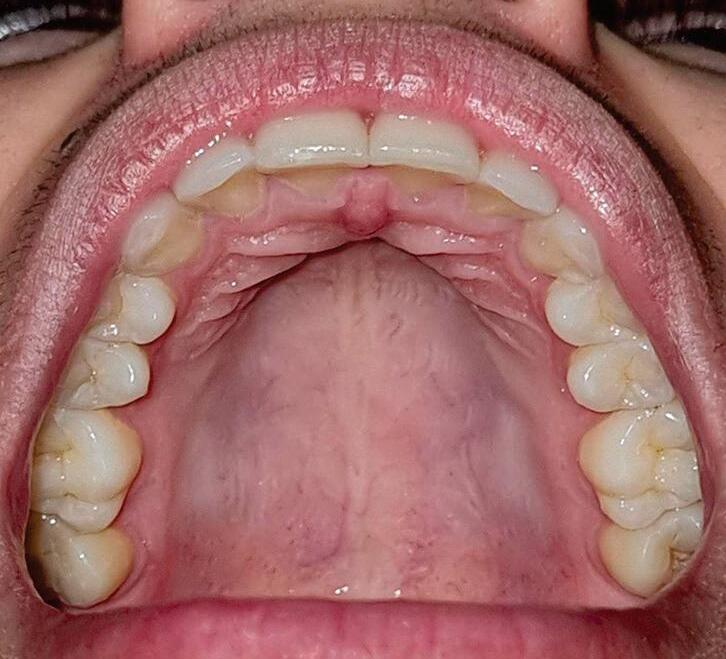

A inspeção do palato revela que a mucosa palatina se estende lateralmente de gengiva palatina direita e esquerda em região de rebordos na maxila. A mucosa anterior do palato duro é firmemente aderida ao osso palatino e apresenta as rugas palatinas. A rafe palatina é uma crista de tecido na linha média que divide o palato duro em duas partes iguais. A palpação dos palatos duro e mole acontece de forma digital, sempre precedida da inspeção e com cautela, devida a atos reflexos da região de úvula (Fig. 1-4).

Fig. 1-4. (a) Palato duro. Observar presença da rafe palatina, das pregas palatinas anteriores e de uma mucosa firme e mais descorada. (b) Transição palato duro e palato mole.